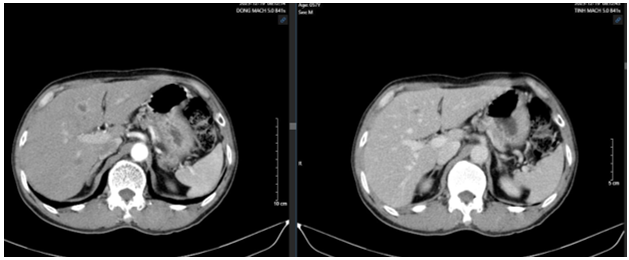

- CT ổ bụng: Hình ảnh vài nốt ngấm thuốc nhu mô gan. Vài hạch dọc động mạch chủ, kích thước lớn nhất 17x10mm

Hình 1. Hình ảnh cắt lớp vi tính ổ bụng trước điều trị (hạch dọc động mạch chủ)